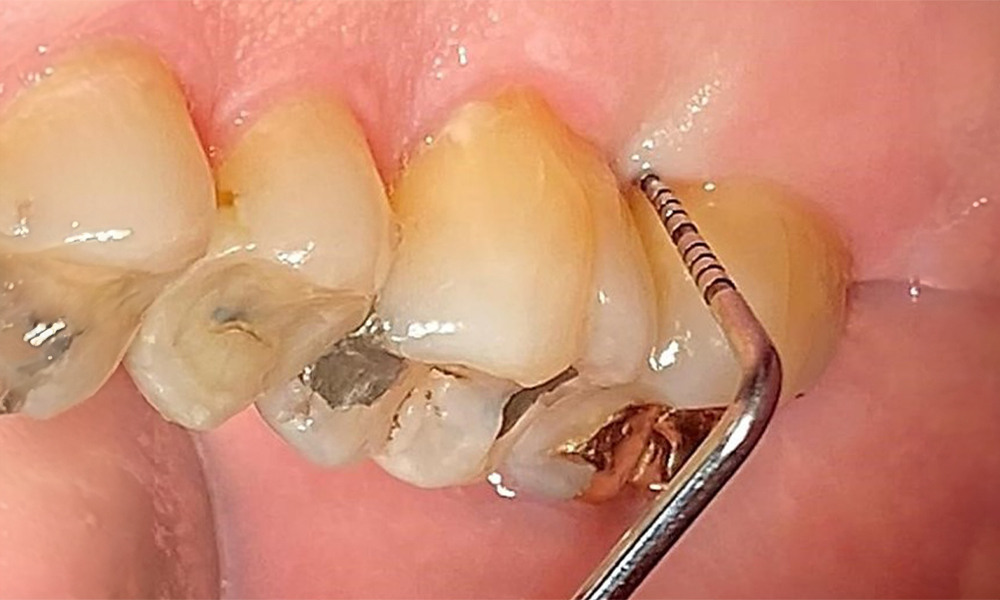

Probing to document the findings in tooth 27 mesiopalatal.

Fig. 8: Probing to document the findings in tooth 27 mesiopalatal. © Dr R. Krapf

The documentation of periodontal findings, including pocket depth probing and bleeding status, is mandatory during each dental appointment due to the presence of periodontitis (Fig. 8). This will record the individual therapeutic needs and facilitate a rapid response to any progression of the pre-existing periodontitis.

Detailed periodontal findings, including the documentation of pocket depths, bleeding on probing, recessions, furcation involvement and degree of loosening, must be examined annually.

This will ensure a rapid response to any potential progression of the pre-existing periodontitis. Examination of the hard tooth structure and root surfaces is also mandatory, since the presence of exposed root surfaces increases the risk of root caries.